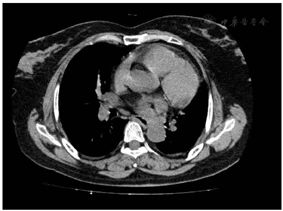

胸部增强CT:双肺下叶炎症,同前;主动脉硬化及肺动脉主干增宽,同前;双侧胸膜增厚较前明显。超声心动图:1.左房腔增大,右房腔稍大;2.室间隔增厚;3.二尖瓣及三尖瓣返流(轻度)。结合检验结果暂不考虑肿瘤、结核、肺部炎症导致的咯血,考虑血管相关性较大,因CT及心脏B超未见发现明显血管畸形,进一步行胸部增强MRA:1.肺动脉高压,双侧肺动脉、肺静脉未见明显栓塞;2.胸部未见明显异常畸形血管。为进一步排除支气管动脉病变行气管支气管三维重建示:1.胸廓入口处气管后壁稍欠光滑、局部略凸起,左侧主支气管周围软组织影,相应管腔狭窄,性质待定,建议增强。2.右上肺前段肺动脉亚段分叉处局部稍膨大,动脉瘤?建议行支气管动脉及肺动脉CTA加二期重建(图1)。因影像提示血管畸形可能性较大,考虑支气管Dieulafoy病变可能性较大,为进一步明确诊断于完善病理检查,遂行支气管镜检查(左主气管黏膜)送检支气管黏膜组织病理:上皮鳞状化生,黏膜下血管扩张,大量淋巴细胞及少量嗜酸性粒细胞浸润,组织改变为支气管黏膜慢性炎(图2)。结合支气管动脉CT造影提示血管畸形及病理发现血管畸形扩张,明确诊断:支气管动脉畸形(Dieulafoy病)。

本例患者胸片和胸部CT没有发现异常,气管支气管三维重建显示胸廓入口处气管后壁稍欠光滑、局部略凸起,左侧主支气管周围软组织影,相应管腔狭窄,右上肺前段肺动脉亚段分叉处局部稍膨大,动脉瘤待排。在支气管镜下进行组织活检,送检支气管黏膜组织显示上皮鳞状化生,黏膜下血管扩张,大量淋巴细胞及少量嗜酸性粒细胞浸润,组织改变为支气管黏膜慢性炎。根据病人临床症状,影像学检查和病理结果,诊断为支气管Dieulafoy病。文献报道支气管Dieulafoy病支气管镜下常表现为黏膜完整的突向管腔的光滑突起样病灶,个别有轻微搏动,有时突起表面覆盖有黄白色渗出物,易被误认为腔内肿瘤结节[11],但是这种镜下病变是非特异性的,有小于1cm的,覆盖正常黏膜的突起或结节,就应该考虑支气管Dieulafoy病[12]。组织活检有可能导致致命的出血,刘旭[13]和李俊涛[14]都曾报道病人在做支气管镜检查取材活检时发生大咯血甚至导致失血性休克,由于较充足的术前准备,我们在病理活检时虽未发生大出血事件,但应值得警惕在活检时导致血管破裂出血导致呼吸道堵塞以及失血性休克等不良事件发生。尽管病理诊断为"金标准",但我们建议对怀疑Dieulafoy病患者应谨慎考虑组织病理检查,如果病理检查对诊断和治疗的必要性非常大,应在EBUS检查评估和充足术前准备下进行。